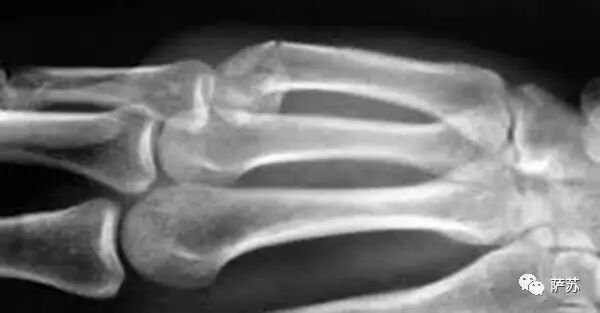

原来,黑大个的手骨折得十分蹊跷,第五掌骨颈骨折,而且狀如磕头。从法医学角度,这种伤叫做“Boxer's fracture”,俗称“拳击手骨折伤”。

▲ 黑大个的拳击手骨折伤,可以清楚看到第五掌骨颈(最上方)已经变形折断

这种伤,不可能是别人打击形成的,它形成的原因是拳击对手过猛或击在硬物比如墙壁上时,掌骨承受不住冲击力而自行折断。因为较多发生在拳击手身上而得名。

这种伤不明显,通常无剧烈痛感,也不肿胀,只是手握不紧,小拇指关节感觉不在位置上,拳击手骨折伤常常要到照片子才会被发现。没有经验的医生不大会意识到它是怎样造成的,但这位老法医偏巧是潜心研究成伤机制多年的,所以一看片子便心中有数。